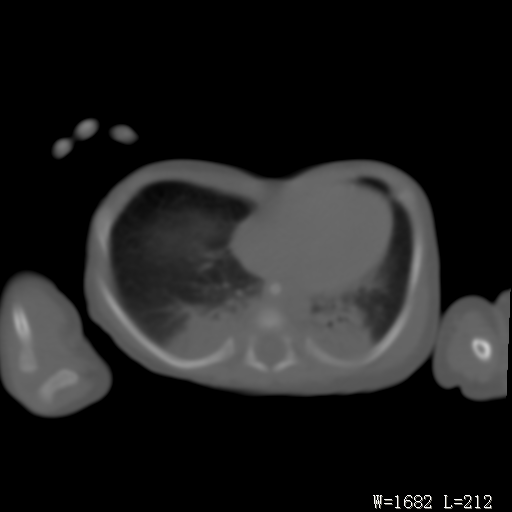

以下是引用改行者在2010-7-8 22:13:00的发言:[br]两肺野透光度降低伴细颗粒状影,两肺下叶见实变影,其内见支气管充气征。 多考虑新生儿肺透明膜病。